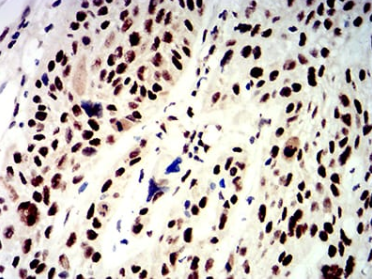

IHC    1/200 - 1/1000